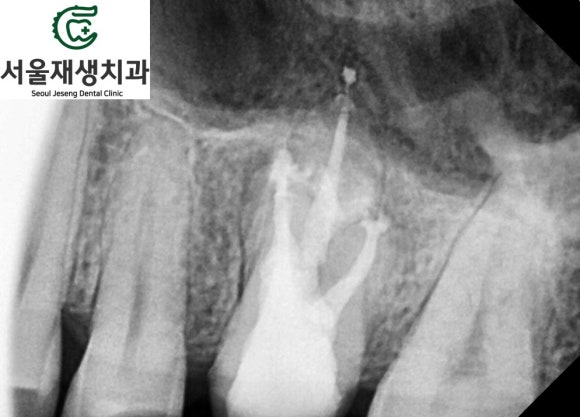

3차 신경치료를 시작합니다 (두둥)

이전 치료에서 미흡했던 부분을 집중 공략했습니다.

두둥.

신경관을 통해 뿜어져 나오는 대량의 고름....

열심히 청소하고 소독합니다.